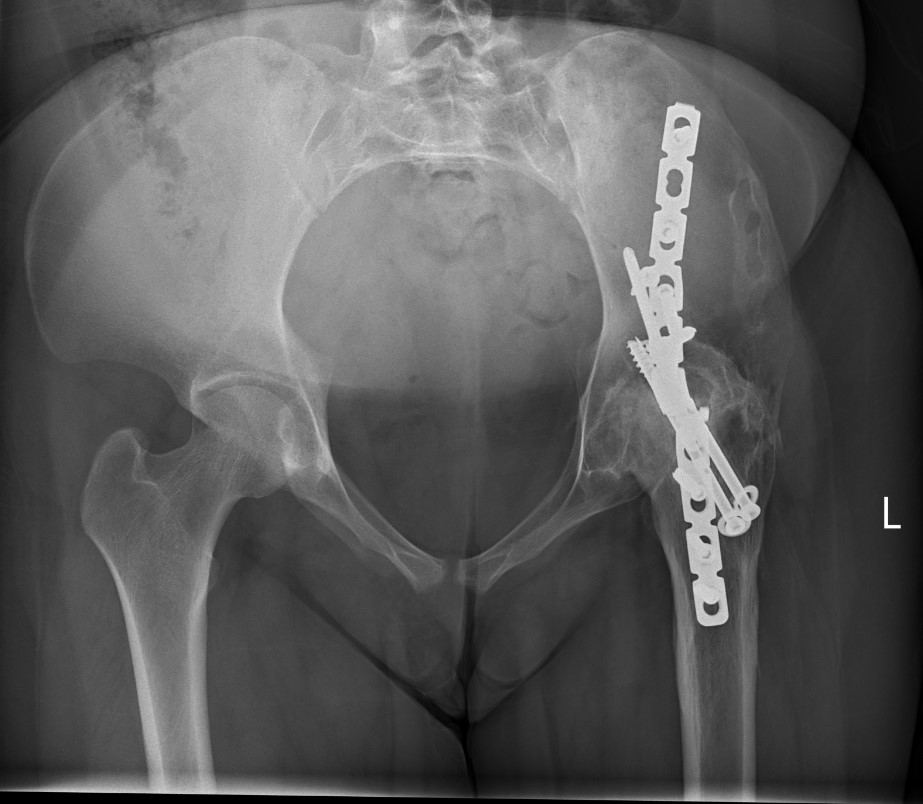

Extra-articular Intra-articular Combined intra-articular + anterior plate

Hip Fusion Cobra Plate Hip Fusion AP Hip Fusion 1Hip fusion 2

Fixation

- 150° DHS / 6.5 mm cannulated screws

- through joint into thick supra-acetabular area of ilium

- supplement with additional screws as necessary

Anterior plate onto lateral aspect of iliac crest